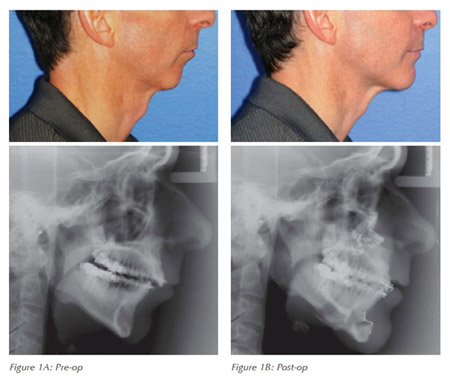

In patients having difficulty with other treatments, surgical procedures for the nose and throat can be a beneficial alternative. Skeletal surgical procedure which involves repositioning the lower and/or upper jaws in a forward manner also proves to be very effective. Surgical therapy can also be effective when used as an adjunct to improve tolerance and success with CPAP or an oral appliance.

YES, once all the lifestyle factors are corrected and jaw and tongue position corrected with Orthognathic surgery, in most cases patient’s dependence on oral appliance and CPAP machine is avoided.

What is exactly done in surgical procedure?